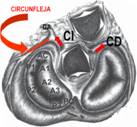

La arteria coronaria izquierda luego de su nacimiento se bifurca (Figura 5) en las arterias descendente anterior que va hacia adelante y la circunfleja que rodea a la comisura anterolateral de la válvula mitral y que puede ser ligada durante la anuloplastia o el reemplazo valvular.

Figura 5 Esquema de la válvula mitral en relación a las demás válvulas cardíacas y la relación con la arteria circunfleja que luego de su bifurcación de la coronaria izquierda rodea la comisura anterolateral mitral